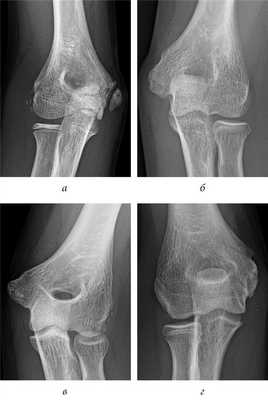

Рис. 5. Заключительные контрольные рентгенограммы: a — несращение; б — двойной контур; в — гиперплазия; г — гипоплазия